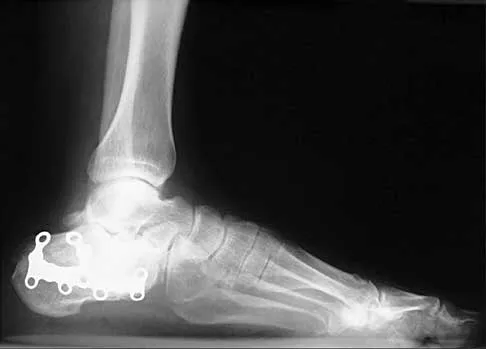

A patient with rheumatoid arthritis with both ankle and subtalar involvement was treated as shown in Figures 11a and 11b. What complication is unique to this type of fixation?

Explanation

The interlocking screws at the proximal end of the rod can act as a stress riser and lead to fracture. Postoperative pain at this level should prompt inclusion of this diagnosis in the differential. Removing the screws following bone union can decrease the chances of this occurring. A short rod that avoids the diaphyseal area may also be beneficial. Rotatory deformity is controlled by the perpendicularly oriented distal transfixion screws. Talar osteonecrosis would be unusual since the dissection can be minimized with an intramedullary rod. Any type of hardware can fail if the construct does not lead to a solid arthrodesis. Nunley JA, Pfeffer GB, Sanders RW, et al (eds): Advanced Reconstruction: Foot and Ankle. Rosemont, IL, American Academy of Orthopaedic Surgeons, 2004, pp 236-237. Thordarson DB, Chang D: Stress fractures and tibial cortical hypertrophy after tibiotalocalcaneal arthrodesis with an intramedullary nail. Foot Ankle Int 1999;20:497-500.